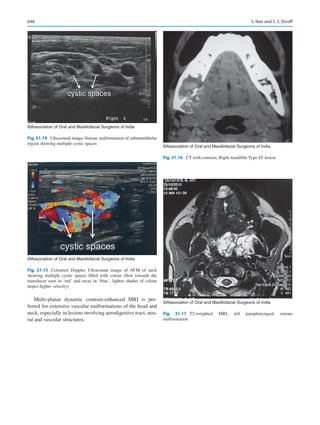

lent in many countries. Several patients are aware of which

chemotherapy may be best effective for the management of

1  Oral and Maxillofacial Surgery in India: How Did We Get Here and Where Are We Going?

6